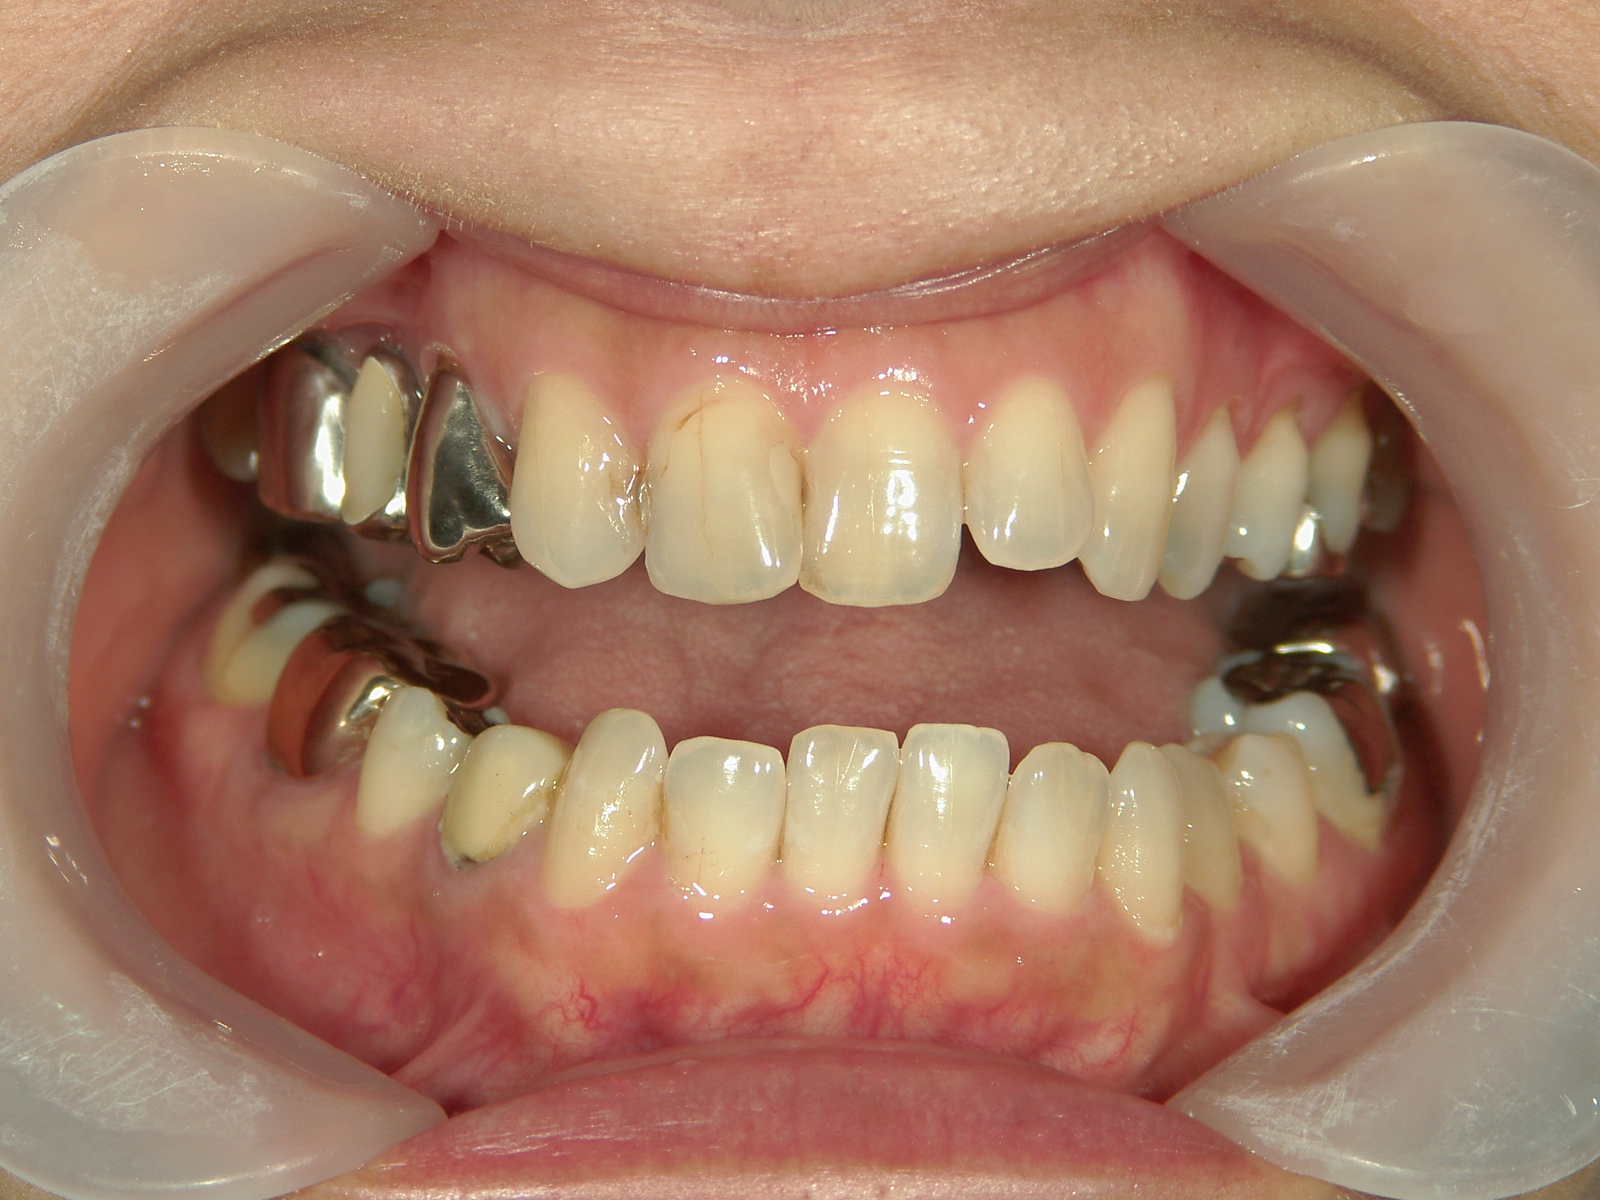

インビザライン矯正 症例(30)

主訴: 受け口、歯並びが気になる。

右下第一小臼歯(1本)、右下親不知(1本)を抜歯。

右下第一大臼歯をセラミックへ変更。

上顎骨切断OPE、矯正装置(MSE+フェイスマスク)、ワイヤー矯正を併用。